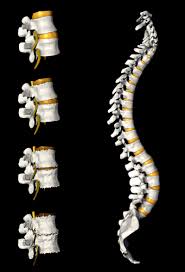

Degenerative disk disease is when normal changes that take place in the disks of your spine cause pain. Spinal disks are like shock absorbers between the vertebrae or bones of your spine. According to the mayfield clinic the disc becomes less flexible and cannot effectively cushion the forces of the adjacent vertebral bones.

Degenerative disc disease commonly occurs in the neck or lower back as you get older. Intervertebral disc degeneration and repair. What is degenerative disc disease.

Degenerative disc disease is an age related condition that happens when one or more of the discs between the vertebrae of the spinal column deteriorates or breaks down leading to pain. Back pain or neck pain when you sit or stand for long periods of time. Degenerative disc disease happens when one or more discs between the vertebrae bones in your spine wear down.